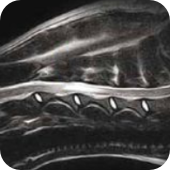

Nowoczesny aparat Esaote zaadaptowany do badań w weterynarii (neurologia, ortopedia, diagnostyka guzów).

Zestaw specjalistycznych cewek odbiorczych dedykowanych konkretnej okolicy ciała zwierzęcia.

Obrazowanie 2D i 3D (RM trójwymiarowe) dla precyzyjnej analizy zmian chorobowych.

Badania z podaniem kontrastu, zwiększające szczegółowość obrazowania.